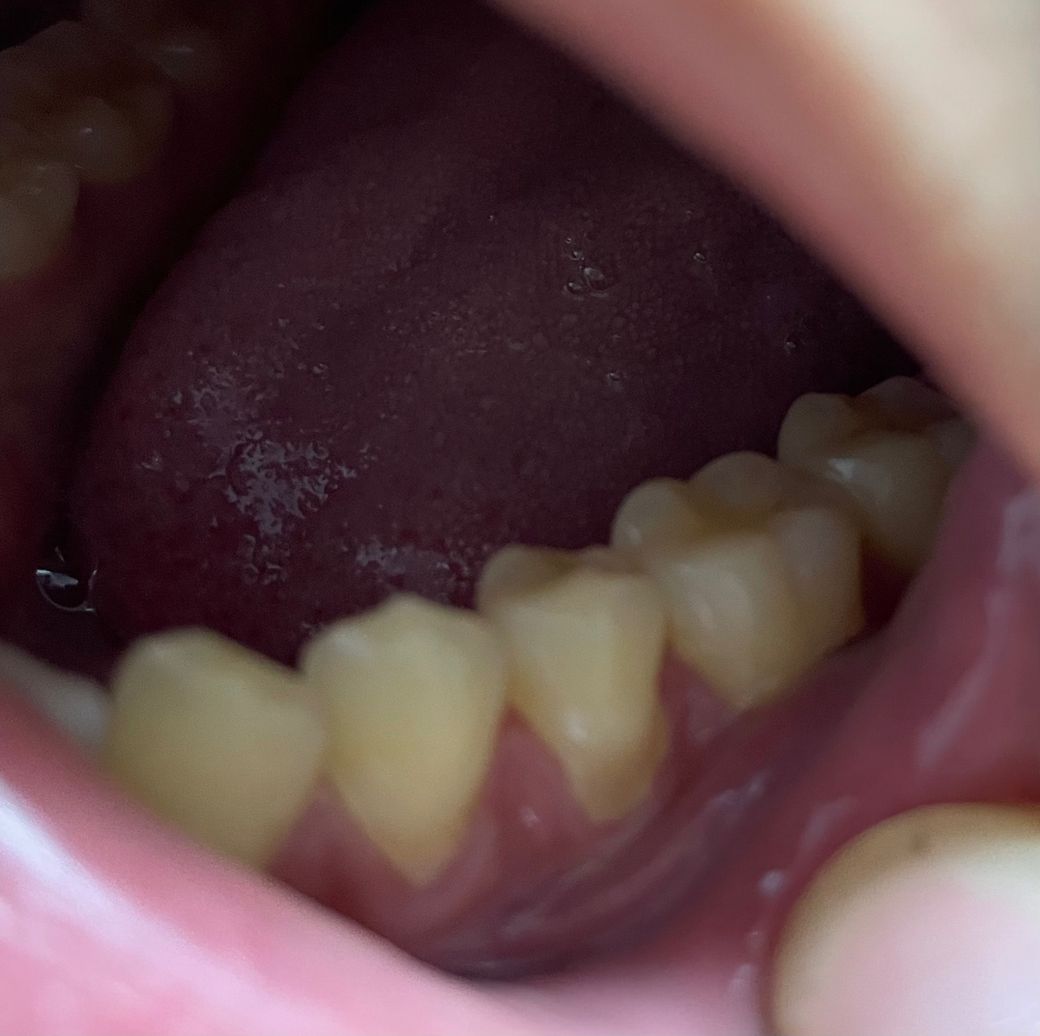

• 2번 째 사진

사진으로 봤을 경우에는 치경부위를 레진으로 충전하고 난다음에 잇몸위로 재료가 덮혀 있는것으로 보입니다.

이런경우 간단하게 치경부레진을 다듬어 줄수 있습니다.

사진으로 봐서는 레진 자체의 문제보다는 치석이 좀 쌓여있는 것 같습니다 치석제거하고 레진 폴리싱하고 다시 봐야 할 것 같습니다